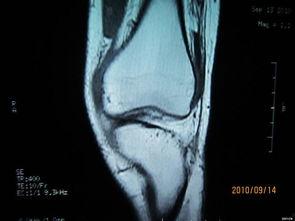

首先,得弄明白什么是膝关节积液。简单来说,就是关节腔内多了一些不该有的液体。这些液体可能是由于关节损伤、炎症、感染等原因造成的。当关节腔内液体过多时,就会导致关节肿胀、疼痛,甚至影响正常活动。

首先,医生会在你的膝关节上做一个小的切口。别担心,这个切口很小,恢复起来也很快。医生会插入一根细长的针,通过这个针将多余的液体抽出来。这个过程可能会有些疼痛,但医生会给你打麻药,所以你不用担心。

抽水后,你会发现膝盖肿胀的情况明显减轻,疼痛也有所缓解。当然,这并不意味着问题完全解决了。医生可能会建议你进行一些物理治疗,以增强关节的稳定性和灵活性。